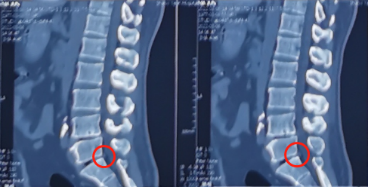

术前影像学资料

刘大姐来陕西冶金医院神经脊柱科了两次:第一次因为剧烈的腰痛和右腿疼痛,当时她疼得右边腿都抬不起来,走路只能扶墙走,平时活动离不开腰围,检查后发现她的腰5骶1处发生了突出,并严重地压迫、刺激到神经根。这种情况熊东主任建议刘大姐进行微创手术治疗,但是由于惧怕手术,她还是选择了保守治疗,并在神经脊柱科进行了康复理疗,症状缓解后出院。